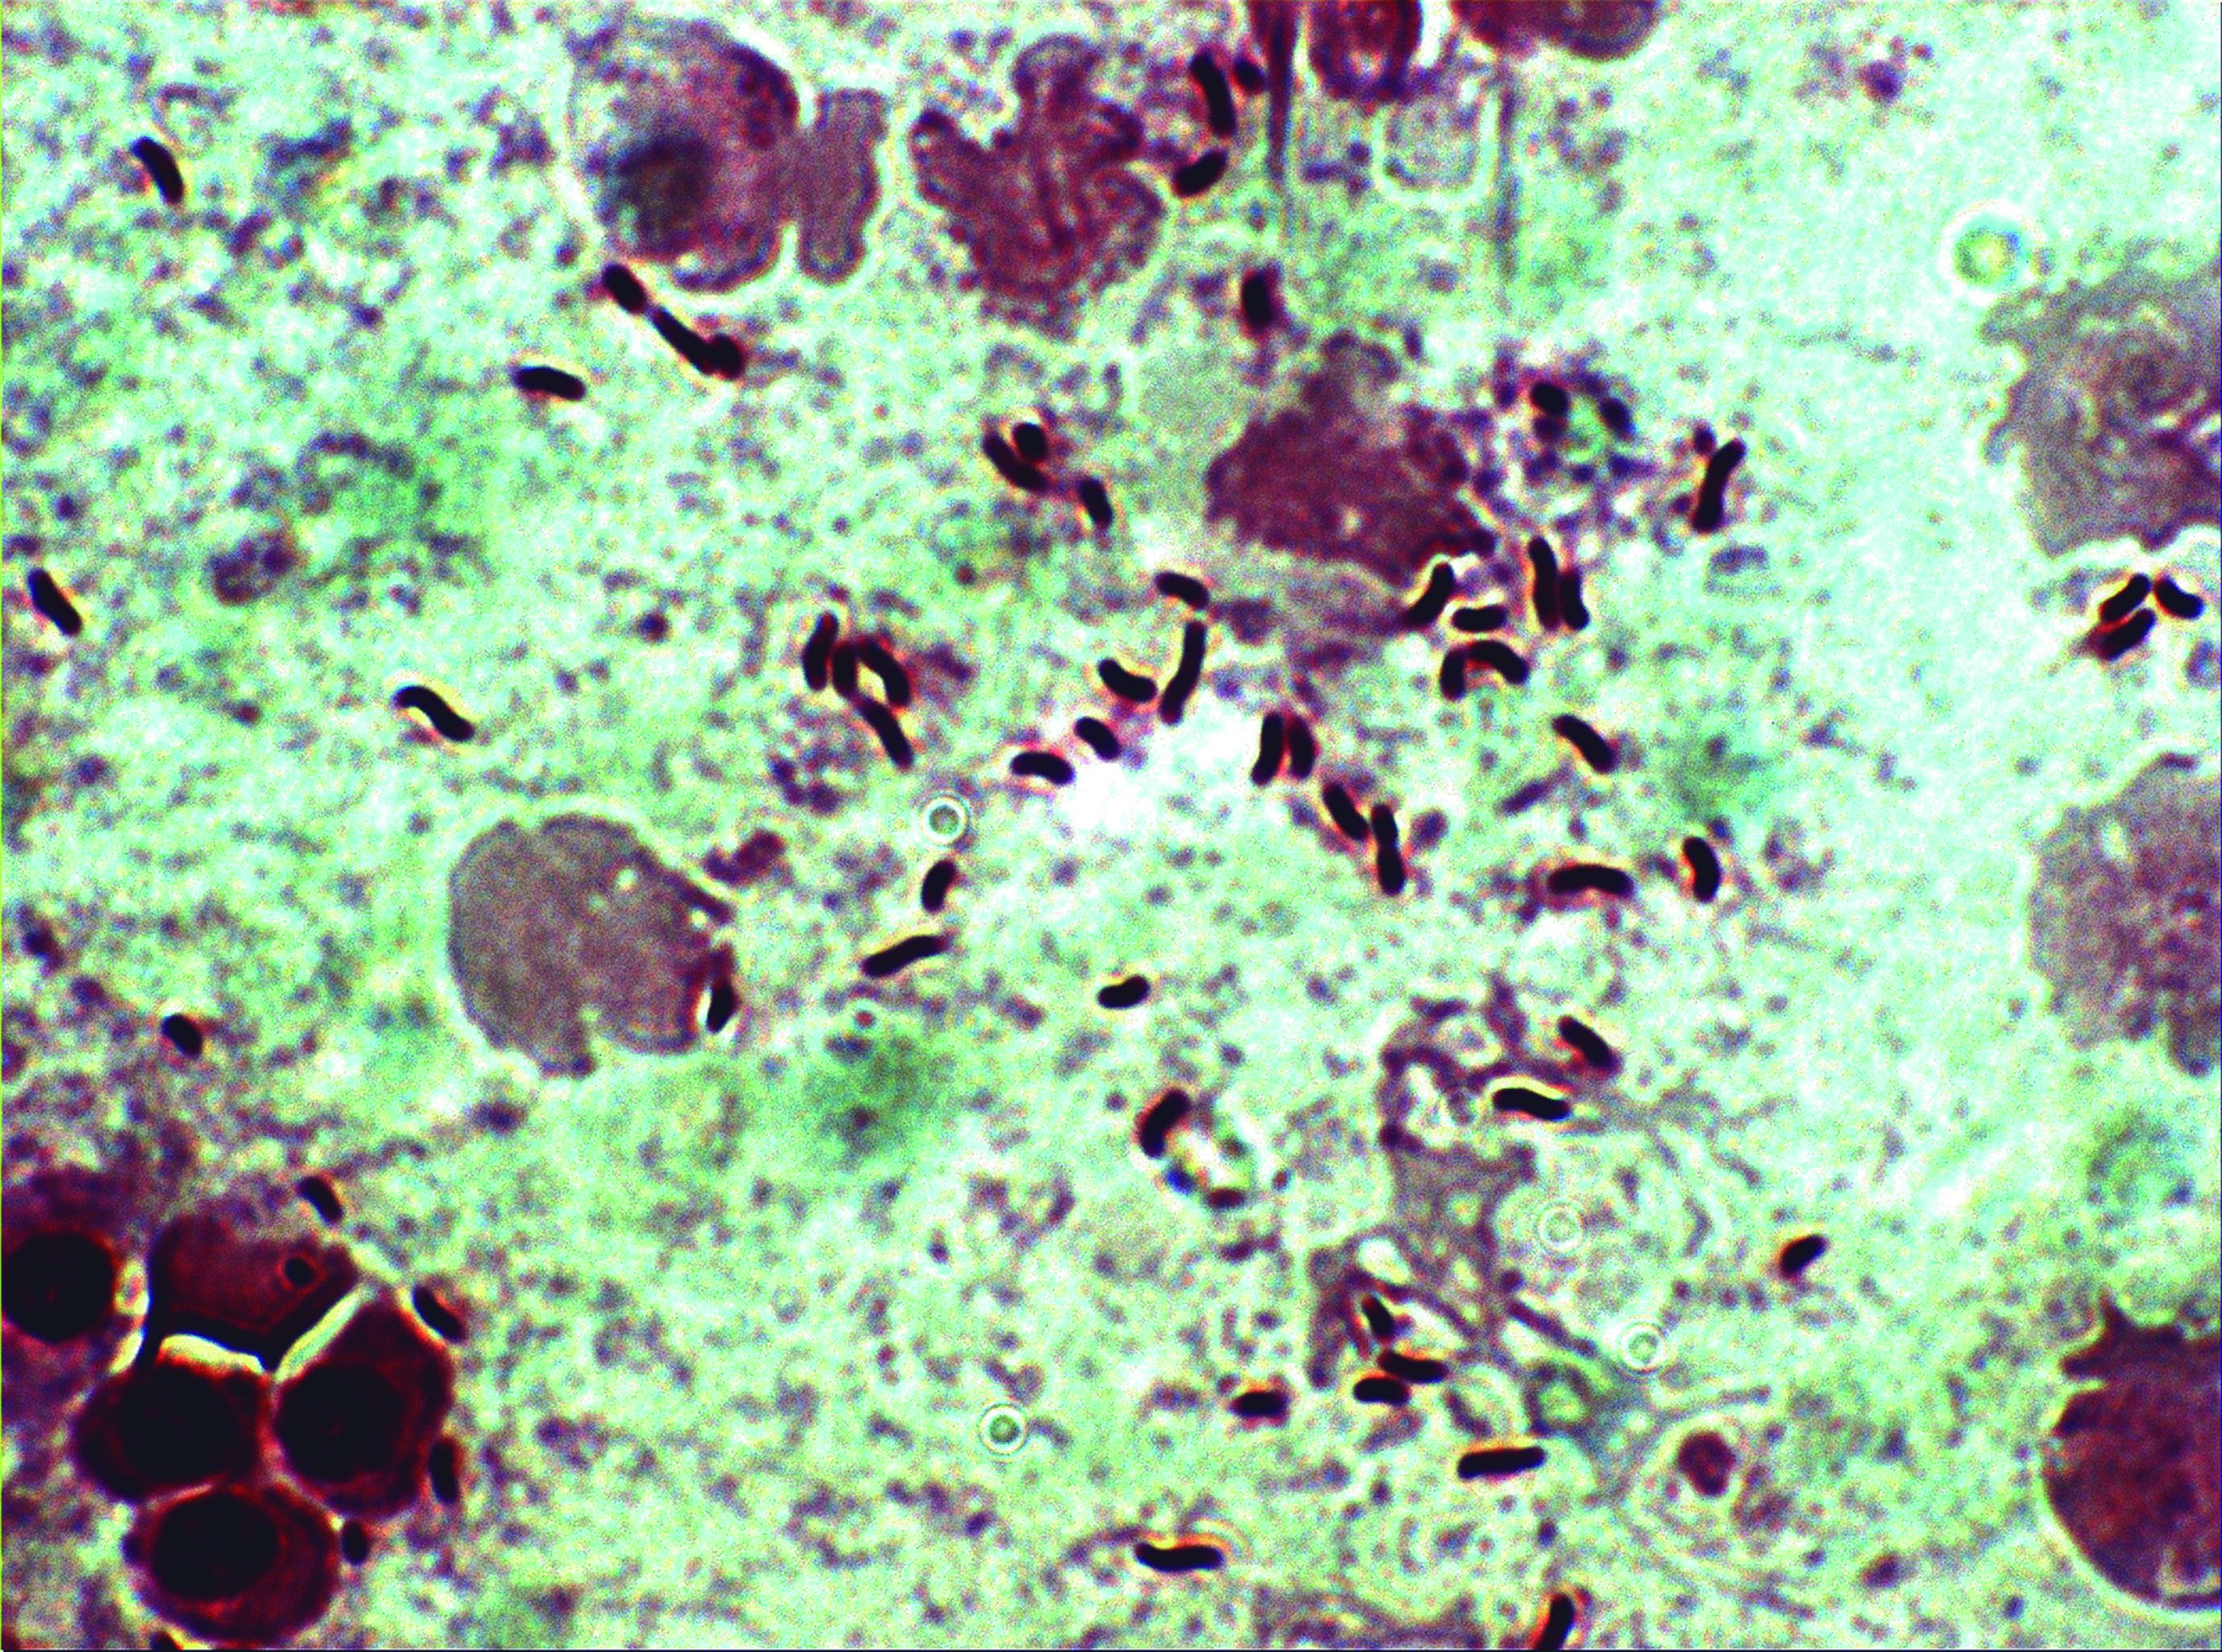

Micobatteriosi

Agente: Mycobacterium spp. (Mycobacteriaceae, piccoli bacilli a forma di bastoncino Gram-positivi resistenti agli acidi-alcol).

Sintomi: Una malattia cronica caratterizzata da lesioni emorragiche e ulcerative esterne, perdita di peso e granulomi negli organi interni. Si verifica in acqua calda. I micobatteri sono zoonotici, quindi i pesci colpiti devono essere prontamente rimossi. Alcune specie di Mycobacterium sono pigmentate di giallo o arancione quando vengono coltivate.

Controllo: Il trattamento è impegnativo, scarsa risposta agli antibiotici.